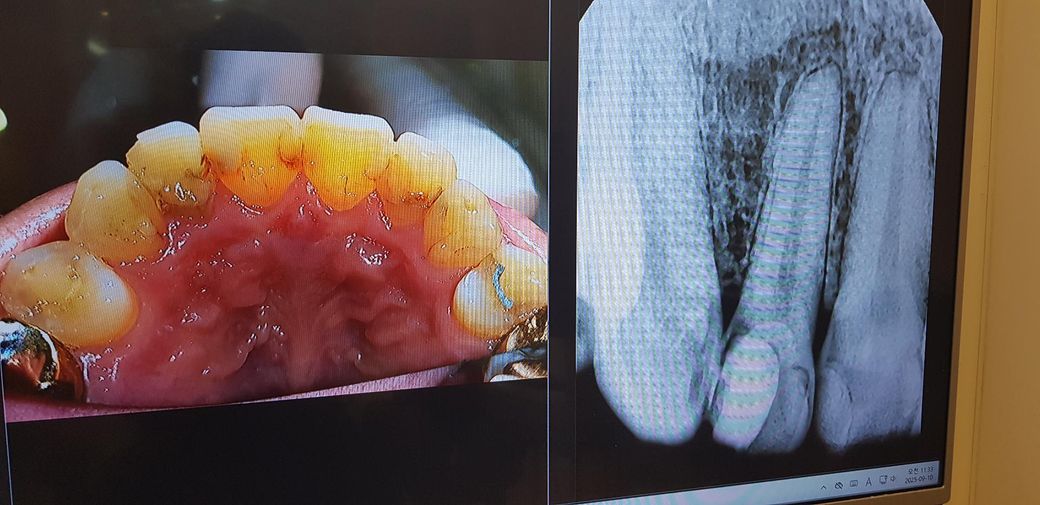

치과 엑스레이 충치 관련한 질문입니다.

저 11번 파절된 치아가 충치 상태인지

충치 상태라면 육안으로 보이는 부위인지

충치 진행도는 어느정도인지 궁금하네요.

사진에 보이는정도면 기존 수복물을 제거하게되면 신경치료를 하셔야될것같습니다. 엑스레이 상으로는 충치가 상당히 깊어 보입니다.

사진으로 봤을 때 치아 주변으로 많은 부위가 충치 이환된 것으로 보입니다. 충치를 제거했을 경우 신경이 노출될 수 있으며 신경치료를 하고 나서도 크라운을 지지할 힘이 약하다면 기둥을 제작해야 할 수 있습니다.

12(측절치),13(송곳니)번 치아는 육안이나 방사선 사진상으로나 충치가 있어보입니다. 특히 12번은 애초에 깊은 충치를 신경치료 없이 떼워둔 상태인데 하방으로 충치가 있어서 신경치료 가능성도 있을 것 같습니다